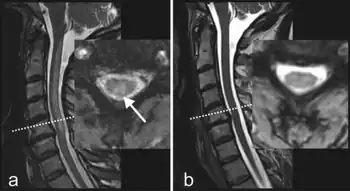

MRI-T2 images may reveal increased signal within the white matter of the spinal cord, predominantly in the posterior columns and possibly in the spinothalamic tracts.